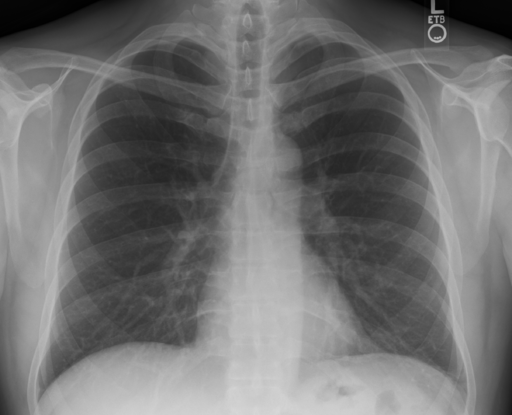

While the natural question is how to reduce the backlog, the underlying, more important question is: "What test allows physicians to be content waiting 30 days for a clinical result?" That problem does not require an algorithm; it requires a discussion, presumably within the NHS, regarding the purpose of these tests. There are limited reasons to order a chest X-ray: as part of a protocol, or to diagnose or follow up on a clinical problem.

In the U.S. a pre-operative chest X-ray is a typical protocol-driven test. As Choosing Wisely, the program to reduce unnecessary testing points out, while many hospitals require them and that number is decreasing, as pre-operative chest X-rays are largely unnecessary outside limited conditions. The necessity for a rapid answer to a diagnostic X-ray should be self-evident. Perhaps a 30 window is acceptable if you're following up on a diagnostic problem? More often than not those problems involve cancer or infection, and chest X-rays are just not the best imaging option.

Examination requires time. Looking at a patient’s chest as they breathe, tapping the various areas of the chest to listen for hollow versus dull sounds, and then listening to the lungs front and back takes a minute, even two. And that doesn’t include the additional minutes required to enter the findings into the electronic record. Before you know it, a third of that 15-minute visit is lost – and that doesn’t even allow for time to explain what you might have found, as well as the doctor's treatment plan. By contrast, it takes 15 seconds to order the chest X-ray.